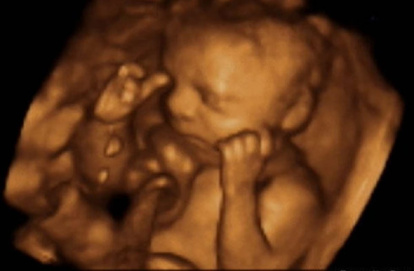

Ecografía 4D de un bebé en el seno de su madre